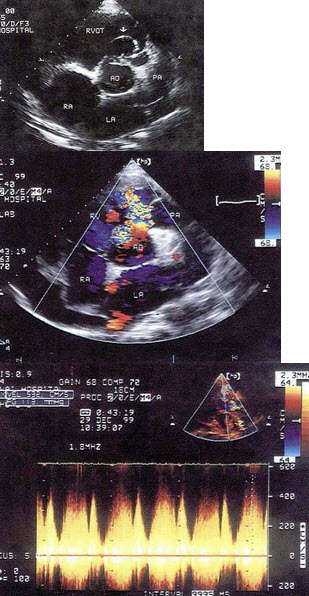

86、单项选择题

该病例最有可能诊断()

A.肺动脉内径增宽

B.动脉导管未闭

C.肺动脉瓣狭窄

D.肺动脉瓣关闭不全

E.右室流出道狭窄